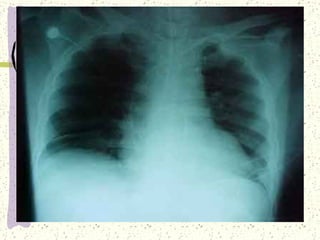

UBICACIÓN DEL CORAZON: Situado en el centro de la cavidad torácica. A la izquierda de la línea media del mediastino y encima del diafragma. El corazón está protegido en la parte anterior por el esternón y posteriormente por la columna vertebral. Los pulmones están situados uno a cada lado.

PERICARDIO: Saco de doble pared, formado por tejido conectivo elástico que protege al corazón del traumatismo y la infección. En su parte inferior, se adhiere al centro del diafragma; en la zona anterior, se une al esternón y en la posterior al esófago, la tráquea y los bronquios principales. El pericardio,  fija el corazón al tórax e impide que se desplace